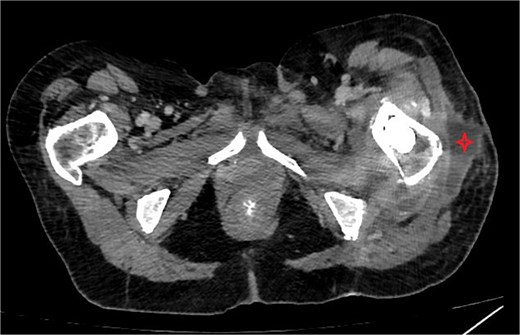

One week after the second stage DAIR, lab tests showed WBC 7500 (63% neutrophils), ESR 102, and CRP 48. CT abdomen and pelvis with IV contrast at 2 weeks did not show any intraabdominal collection or fistula suspicious of primary source of seeding, however it showed fluid collection in the left psoas muscle extending to the iliacus (8.7 × 2 × 1.5 cm), suggestive of deep abscess formation (Fig. 5) with superficial collection in vicinity of left proximal femur (Fig. 6). The latter collection was superficial and was drained at the bedside, releasing non-purulent fluid. The deep abscesses were drained by interventional radiology and a pigtail catheter was inserted for 1 week. Cultures from the deep collection grew K. pneumoniae susceptible to meropenem, which was used to replace ceftriaxone.

CT abdomen/pelvis showing subcutaneous collection at the upper lateral aspect of the thigh in the vicinity of the left proximal femur.